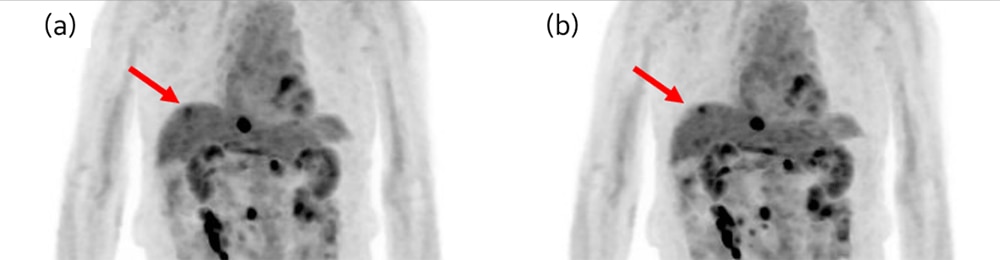

AMF収集を用いることによって、ほとんどの症例でミスレジストレーションと集積のボケが改善されました(図4)。

図4:上行結腸癌術後、再発疑いにて転移検索

(a) 通常収集、(b) AMF収集